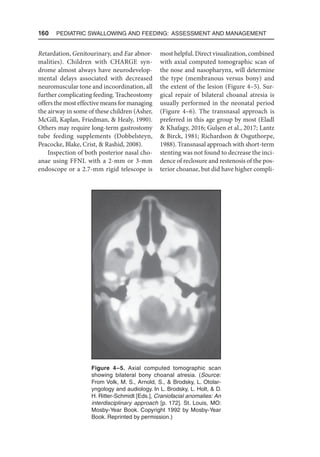

region to another. Taste stimulation alone

is a weak stimulus for swallowing (Dodds,

1989), although the degree of sweetness

of the fluid appears to be one type of sen-

sory input for infants (Burke, 1977). Light

touch is the most effective stimulus at the

faucial pillars, heavy touch in the posterior

pharynx, and water at the posterior larynx

(Shinghai  Shimada, 1976; Storey, 1968).